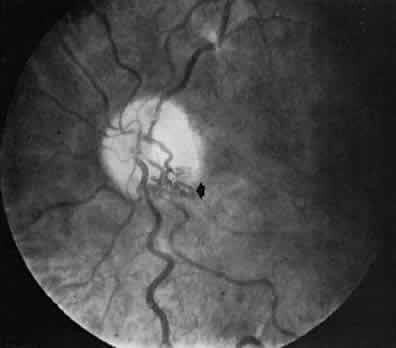

In as many as 20% of normal eyes, a cilioretinal artery may exist as well.11 These are vessels that directly connect the posterior ciliary circulation to the retinal circulation. Clinically, they can usually be identified by their ophthalmoscopic appearance. Cilioretinal vessels emerge from the edge of the optic disc, with no apparent connection to the central retinal vessels (Fig. 2). Fluorescein angiography shows them to fill with the choroidal circulation. They are usually temporally located on the optic disc but rarely can be nasal. Multiple vessels may be present. Cilioretinal arteries are the easiest to identify. The existence of cilioretinal venous channels in normal eyes is a subject of debate.12 Acquired cilioretinal veins, referred to as optociliary anastomoses or incorrectly as optociliary shunts, can develop in pathologic processes such as obstruction of the CRV or in optic nerve tumors (Fig. 3).

Fig. 2. The cilioretinal artery hooks around the temporal margin of the disc edge (*). (Henkind P, Benjamin JV: Trans Ophthalmol Soc UK 96:418, 1976)

Fig. 3. An opticociliary vein developing in an elderly patient after a central retinal vein occlusion. The vein appears as a tortuous vessel, inferotemporally (arrow). (Henkind P, Benjamin JV: Trans Ophthalmol Soc UK 96:418, 1976)